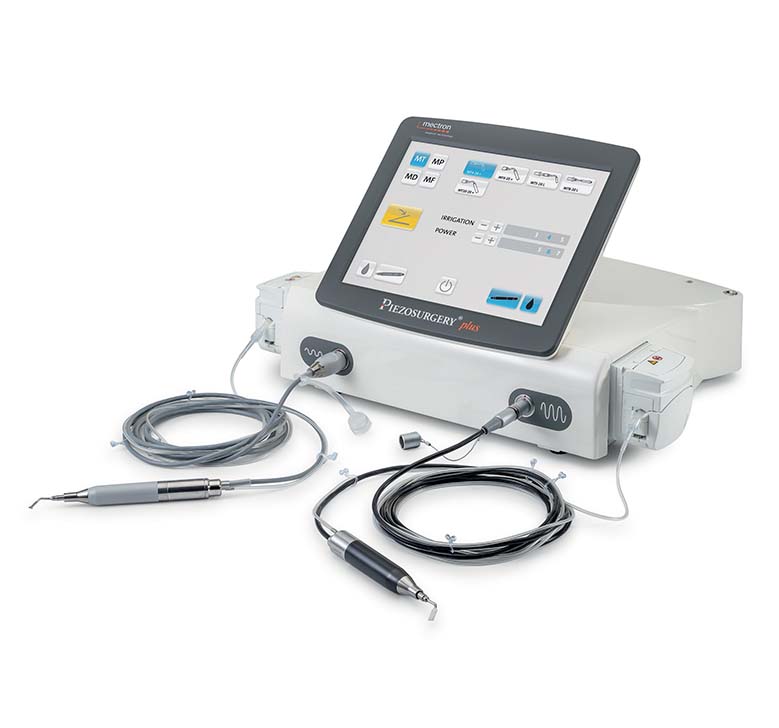

PIEZOSURGERY® plus

DESIGNED TO BE COMPLETE

PIEZOSURGERY® plus is the complete device: it is engineered to support an expansive range of surgical applications in Spine surgery.

Unmatched efficiency, precision, and performance delivered through two independent handpieces and channels.